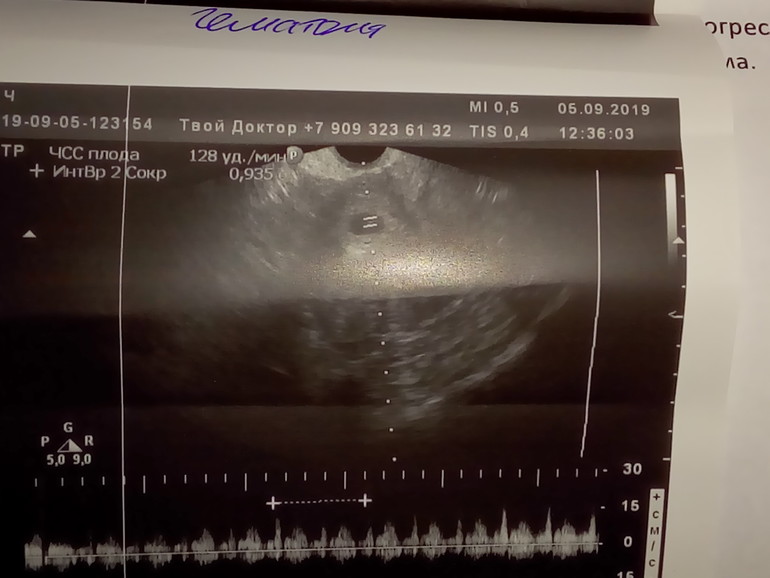

УЗИ в 7 недель и 4 дня

УЗИ, КТГ, доплерНе зря я была спокойна, несмотря на плохие прогнозы в прошлое УЗИ неделю назад.

Назначила врач постельный режим ,половой и физический покой, Транексам 5 дней по 2 таблетки 3раза в день, свечи с папаверином к тому , что я принимаю, а это дюфастон 4 таблетки в день каждые 6 часов, Фемибион 1, Магний В6. Надеюсь рассосётся гематома к 12 неделе. На приём к геникологу и на учёт вставать через 2 недели, анализы дали сдавать целую стопку.

Слышала , что по УЗИ гематома это не 100% она, это может быть просто ещё не плотно прилегает плодное яйцо к матке.